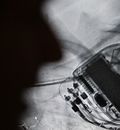

Three reasons why pacemakers are vulnerable to hacking

Malware and Vulnerabilities